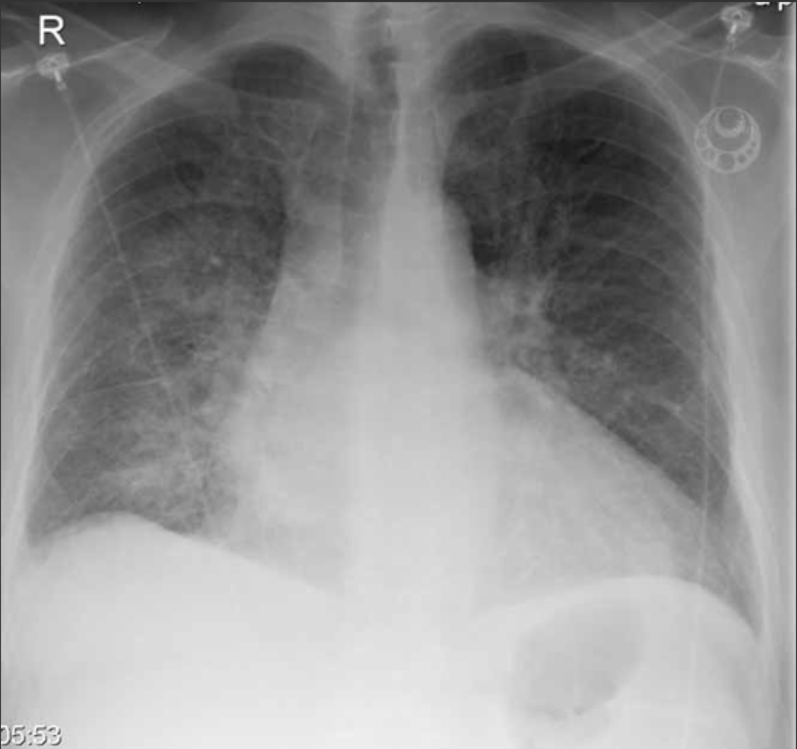

Vad ser du?

Hjärtat är allmänförstorat. Lungkärlen är vida och det finns ökad mängd pleuravätska bilateralt. Det finns spridda interstitiella och basalt på höger sida även alveolära infiltrat.